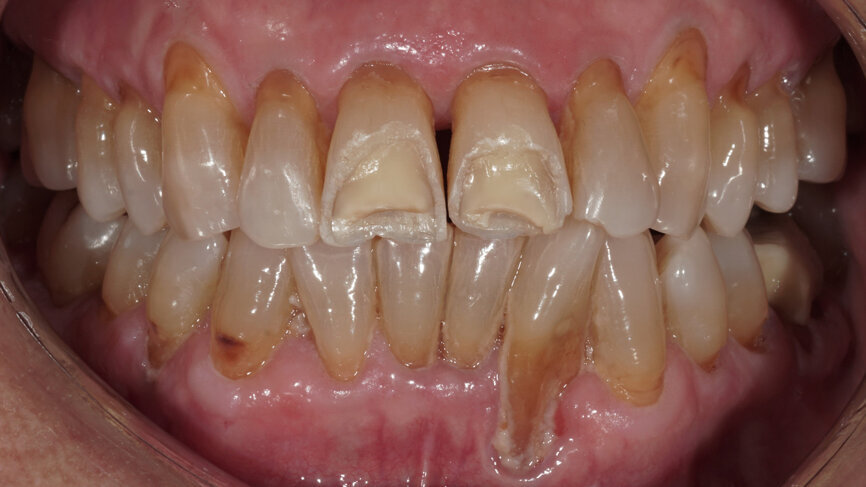

Fig. 2: Clinical situation at the initial appointment in the dental practice.

The 85-year-old female patient presented after osteosynthesis of multiple mandibular fractures she had sustained in a fall (Figs. 1 & 2). During fixation, the left posterior region of the mandible was moved such that teeth #34–37 were brought out of occlusion (Fig. 3). The patient naturally wished to be able to chew properly again in this area. After endodontic treatment of the two avulsed central incisors, which had been replanted in the hospital, and periodontal therapy, occlusal elevation was planned on the left side.

The aim was to restore the teeth and elevate the occlusion with three onlays and a crown made of lithium disilicate (IPS e.max CAD, Ivoclar Vivadent). During tooth preparation, however, a longitudinal root fracture of the first molar was detected. Therefore, only the first premolar was restored in this session. For this purpose, an onlay was produced chairside using the CEREC system (Dentsply Sirona) and adhesively luted with PANAVIA V5 (Kuraray Noritake Dental). The first molar was extracted.

One week later, the extraction socket, which was still healing, was modelled for the ovoid pontic using an electrotome loop. The second premolar and molar were prepared as abutment teeth for a bridge. The bridge was then designed (Figs. 4–6) and milled from KATANA Zirconia Block for Bridge in Shade A3.5 and individualised with CERABIEN ZR FC Paste Stain (both Kuraray Noritake Dental; Figs. 7–10). A further week later, the bridge was luted with the self-adhesive resin cement PANAVIA SA Cement Universal after sandblasting (Figs. 11–13).